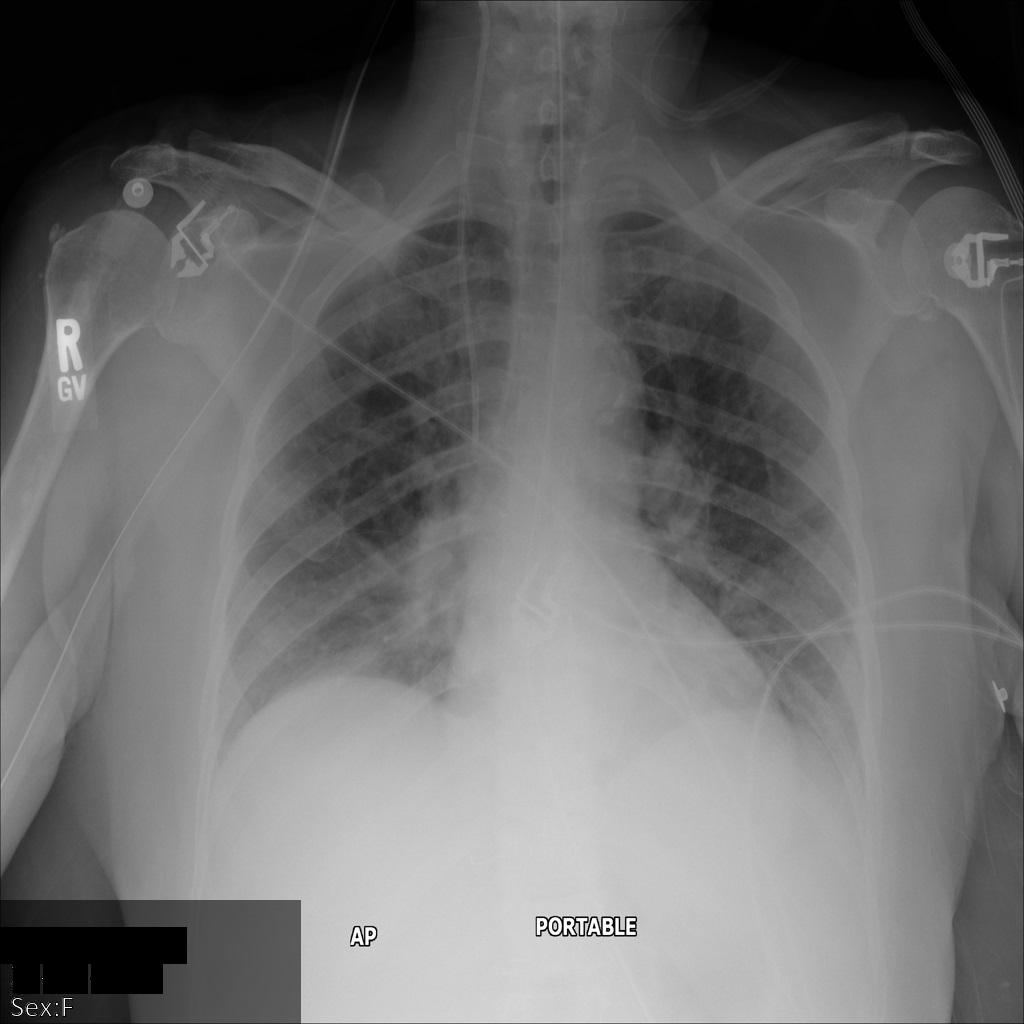

Cada uma das secções seguintes fornece exemplos de como remover a identificação dos dados DICOM usando vários métodos. É fornecida uma saída da imagem desidentificada com cada amostra. Cada exemplo usa a seguinte imagem original como entrada:

Pode comparar a imagem de saída de cada operação de desidentificação com esta imagem original para ver os efeitos da operação.

Depois de enviar a imagem para a Cloud Healthcare API, a imagem aparece

da seguinte forma. Das etiquetas fornecidas na lista de remoção, apenas PatientBirthDate

é removida na imagem, uma vez que é a única etiqueta da lista de remoção que

corresponde a metadados visíveis na imagem.

Embora o PatientBirthDate no canto superior da imagem tenha sido ocultado de acordo com a configuração na lista de remoção, as informações de saúde protegidas incorporadas na parte inferior da imagem permanecem. Para também remover o texto incorporado, consulte o artigo Ocultar texto incorporado em imagens.